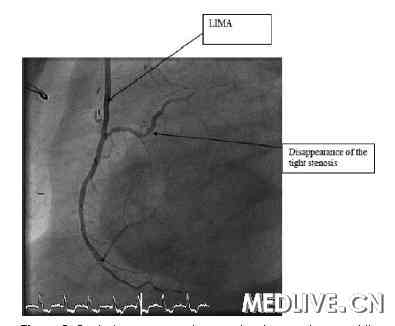

图5. 对照冠状动脉造影显示左乳内动脉通透性良好,

LAD变形部分消失。LIMA表示左乳内动脉。